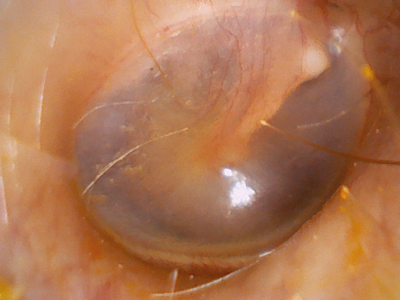

Firefly DE1250 - otoscopy image.

Firefly - DE1250

Type: Wireless endoscopic camera (requires endoscope + light source) Captures images + videos

Cost: £780

Image quality: 75%

Field of view: 100%

Ease of use: 71%

Comments: Good image quality, but also does not have the image capture button in the ideal position as it is too far from endoscope attachment. The live stream to laptop feature is a useful aid to communication, as it allows images or videos to be projected in real time on to a screen visible to the patient during the examination.